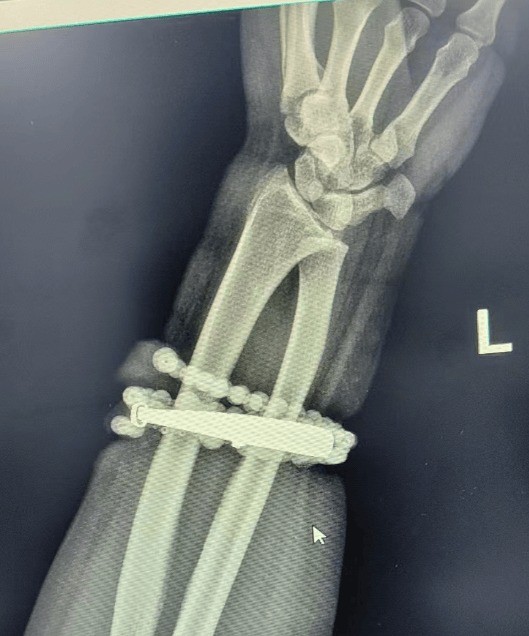

Hình ảnh siêu âm